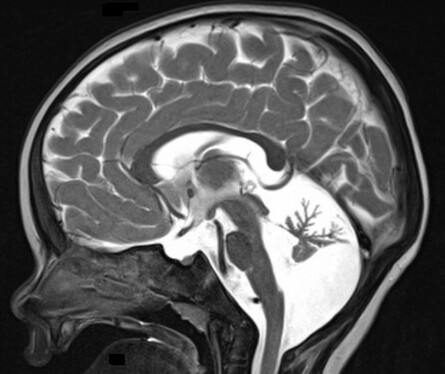

Eine Ataxie kann durch Schädigungen des Kleinhirns oder sensibler Bahnen im Rückenmark verursacht werden. Typisch sind Dysmetrie beim Greifen von Spielzeug, Intentionstremor, skandierende Sprache und breitbasiger unsicherer Gang. Liegt der Ataxie eine Rückenmarksschädigung zugrunde, steht oft die Gangataxie im Vordergrund und die Symptomatik verstärkt sich bei Augenschluss. Früh manifestierende Ataxien treten häufig mit einer Spastik im Rahmen einer ICP auf. Bei Ataxien ohne ICP handelt es sich meist um genetisch bedingte Erkrankungen [2]. Daher ist eine frühzeitige umfassende genetische Abklärung (Next-Generation-Sequencing) sinnvoll. Differenzialdiagnostisch sollte insbesondere an ein Angelman-Syndrom oder ein CDG-Syndrom gedacht werden (Abb. 4). Therapeutisch wichtig ist das Opsoklonus-Myoklonus-Syndrom (Kinsbournesche Enzephalopathie). Charakteristisch sind irreguläre Augenbewegungen und eine ausgeprägte Ataxie. Das Opsoklonus-Myoklonus-Syndrom kann entweder paraneoplastisch bei Neuroblastom oder autoimmunologisch durch Antikörper gegen Kleinhirnstrukturen bedingt sein. Eine möglichst rasche Therapieeinleitung (komplette Tumorresektion und/oder immunsuppressive Behandlung) beeinflusst die Prognose positiv [3].

Abb. 4: Sagittales Kernspintomographiebild mit ausgeprägter Kleinhirnatrophie bei einem einjährigen Jungen mit CDG-Syndrom 1 a und Ataxie.